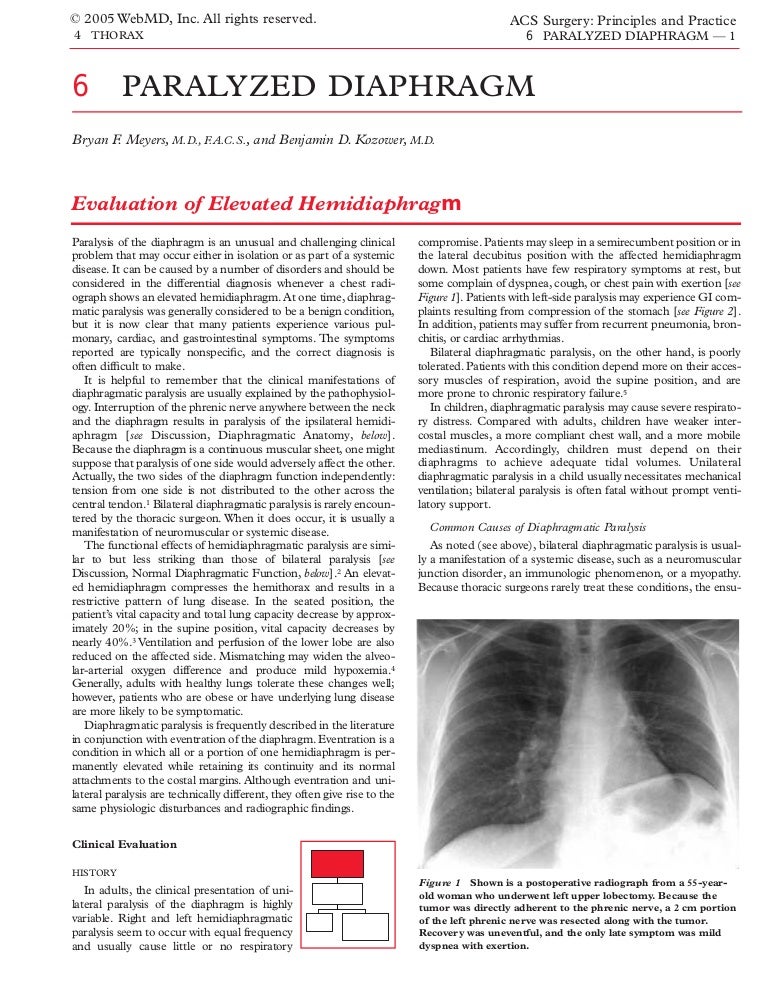

Elevated diaphragm shortness of breath treatment. Eventration of diaphragm 3. A bedside fan or open window with a breeze are also simple but very effective treatments to lessen dyspnea. To treat phrenic nerve irritation This condition can be managed with a breathing pacemaker which takes over the responsibility of sending messages to the diaphragm.

With normal breathing the diaphragm pulls downward and the lungs expand fully. Recovery of diaphragm strength is more variable than recovery of upper limb function and typically takes 25 years12 Although no treatment. Lung cancer and other tumors.

Smoking is the primary cause of emphysema which makes it a preventable illness. Diaphragm weakness due to medical intervention most commonly occurs as a result of physical trauma to the phrenic nerves or diaphragm muscle. Surgical treatment is an option for more advanced cases or if breathing becomes so impacted daily life is affected.

You may not need any treatment. Depending on the severity of injury to the diaphragm some doctors recommend non-surgical options to treat the breathing issues associated with diaphragm weakness and paralysis.